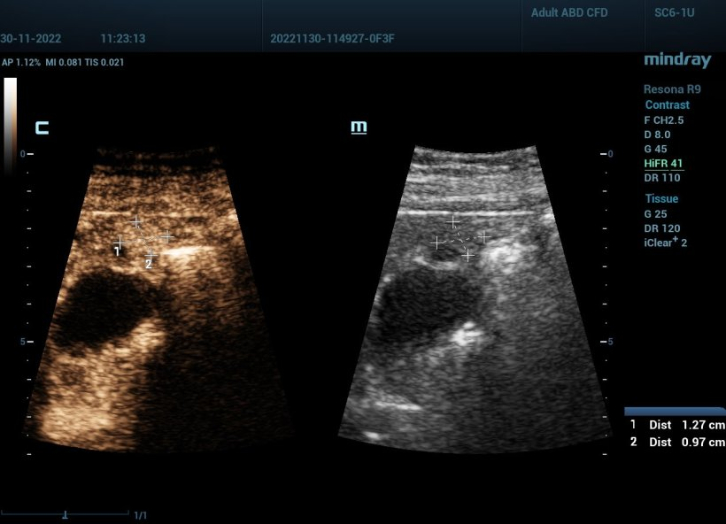

diagnoses-hifr-ceus-fig2

13-миллиметровый полип желчного пузыря рядом с печенью, который не был виден на снимке КТ. Источник изображения: профессор Дитрих